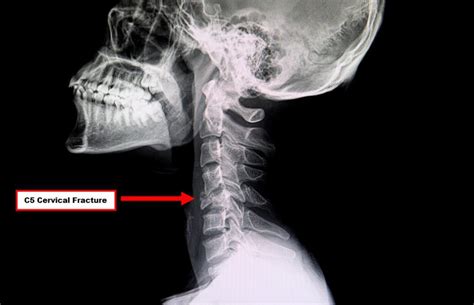

Lee Sumner Blog